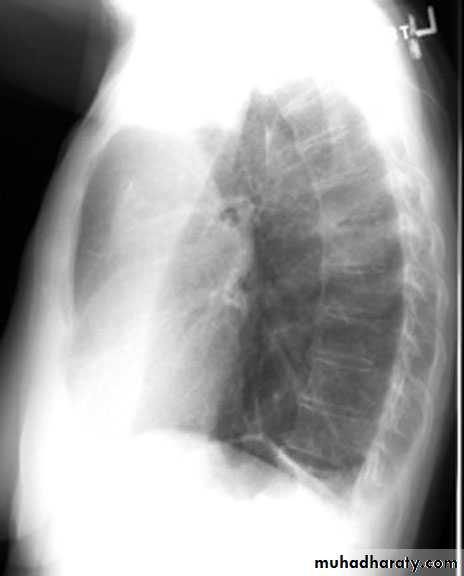

Pleural effusion ( free)

Massive pleural effusion